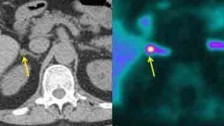

Conn's adenoma Credit: Morris Brown

The test could be especially important for older patients - we often see growths in the adrenal glands during a routine CT scan." - —Morris Brown, Professor of Clinical Pharmacology at the University of Cambridge - A new test developed by researchers at the University of Cambridge could help doctors diagnose thousands of people with the most common curable cause of high blood pressure (hypertension). Research funded by the British Heart Foundation (BHF) and National Institute of Health Research (NIHR), showed a high-tech PET-CT scan could detect Conn's syndrome, which causes up to five per cent of hypertension cases. Around 12 million people in the UK are diagnosed with hypertension, a condition which greatly increases the risk of having a heart attack or stroke. For most people with hypertension there is no single underlying cause, but in a small minority there is a specific condition that causes blood pressure to rise. One of these conditions is called Conn's syndrome - the most common curable cause of high blood pressure. Conn's syndrome is difficult to diagnose but an accurate diagnosis often leads to successful treatment.